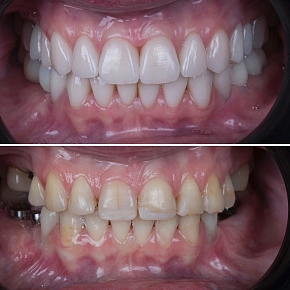

Лечение на элайнерах